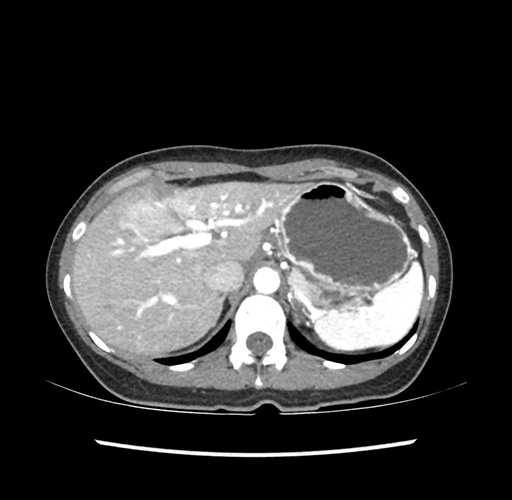

Imaging Analysis

Look through the patient's CT scan to identify any areas of concern for the necessary procedure.

Based on your CT findings, which issue(s) would give reason for "planned slowing down moment(s)" in this case?

Considering a standard left lateral sectionectomy procedure, what step(s) of the operation would you do differently in this case ?